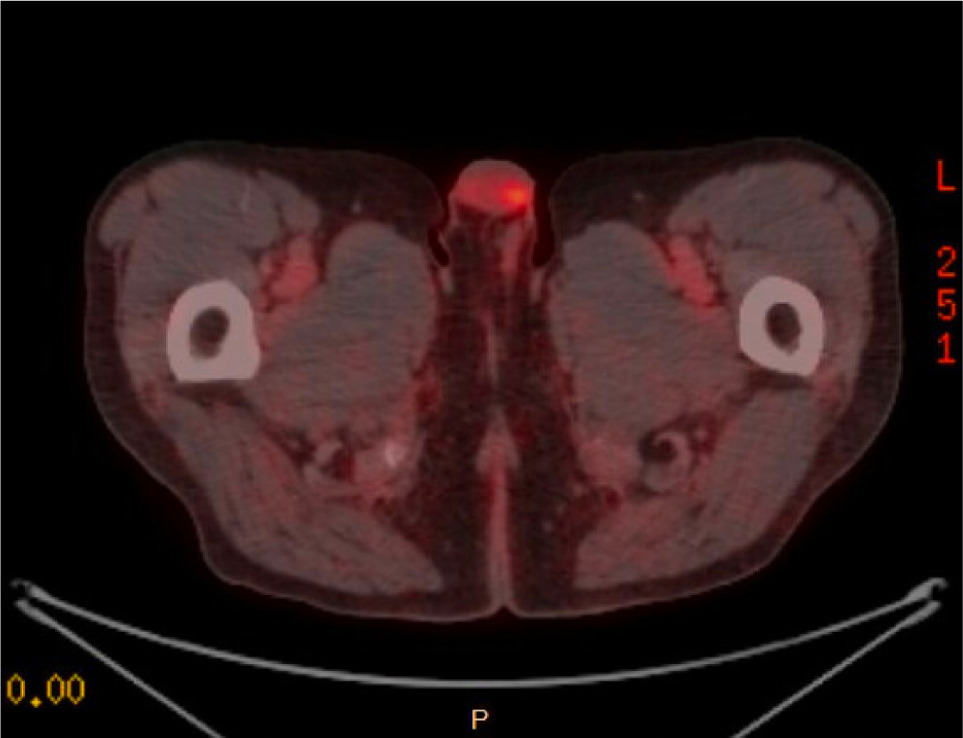

A PSMA–PET/CT scan was performed and was notable for a PET-avid right testicular mass (Figure 1). Subsequent scrotal ultrasound showed a solid, hypervascular 8 mm × 7 mm × 7 mm mass in the right testicle concerning for primary germ cell tumor (Figure 2). Serum tumor markers (AFP, LDH, and HCG) were obtained which were unremarkable. A right radical orchiectomy (Figure 3) was performed with final pathology demonstrating a metastatic clear cell RCC to the testis with lymphovascular invasion (Figure 4).

Figure 1: PSMA-PET demonstrating increased uptake in the right testicle, concerning for metastasis.